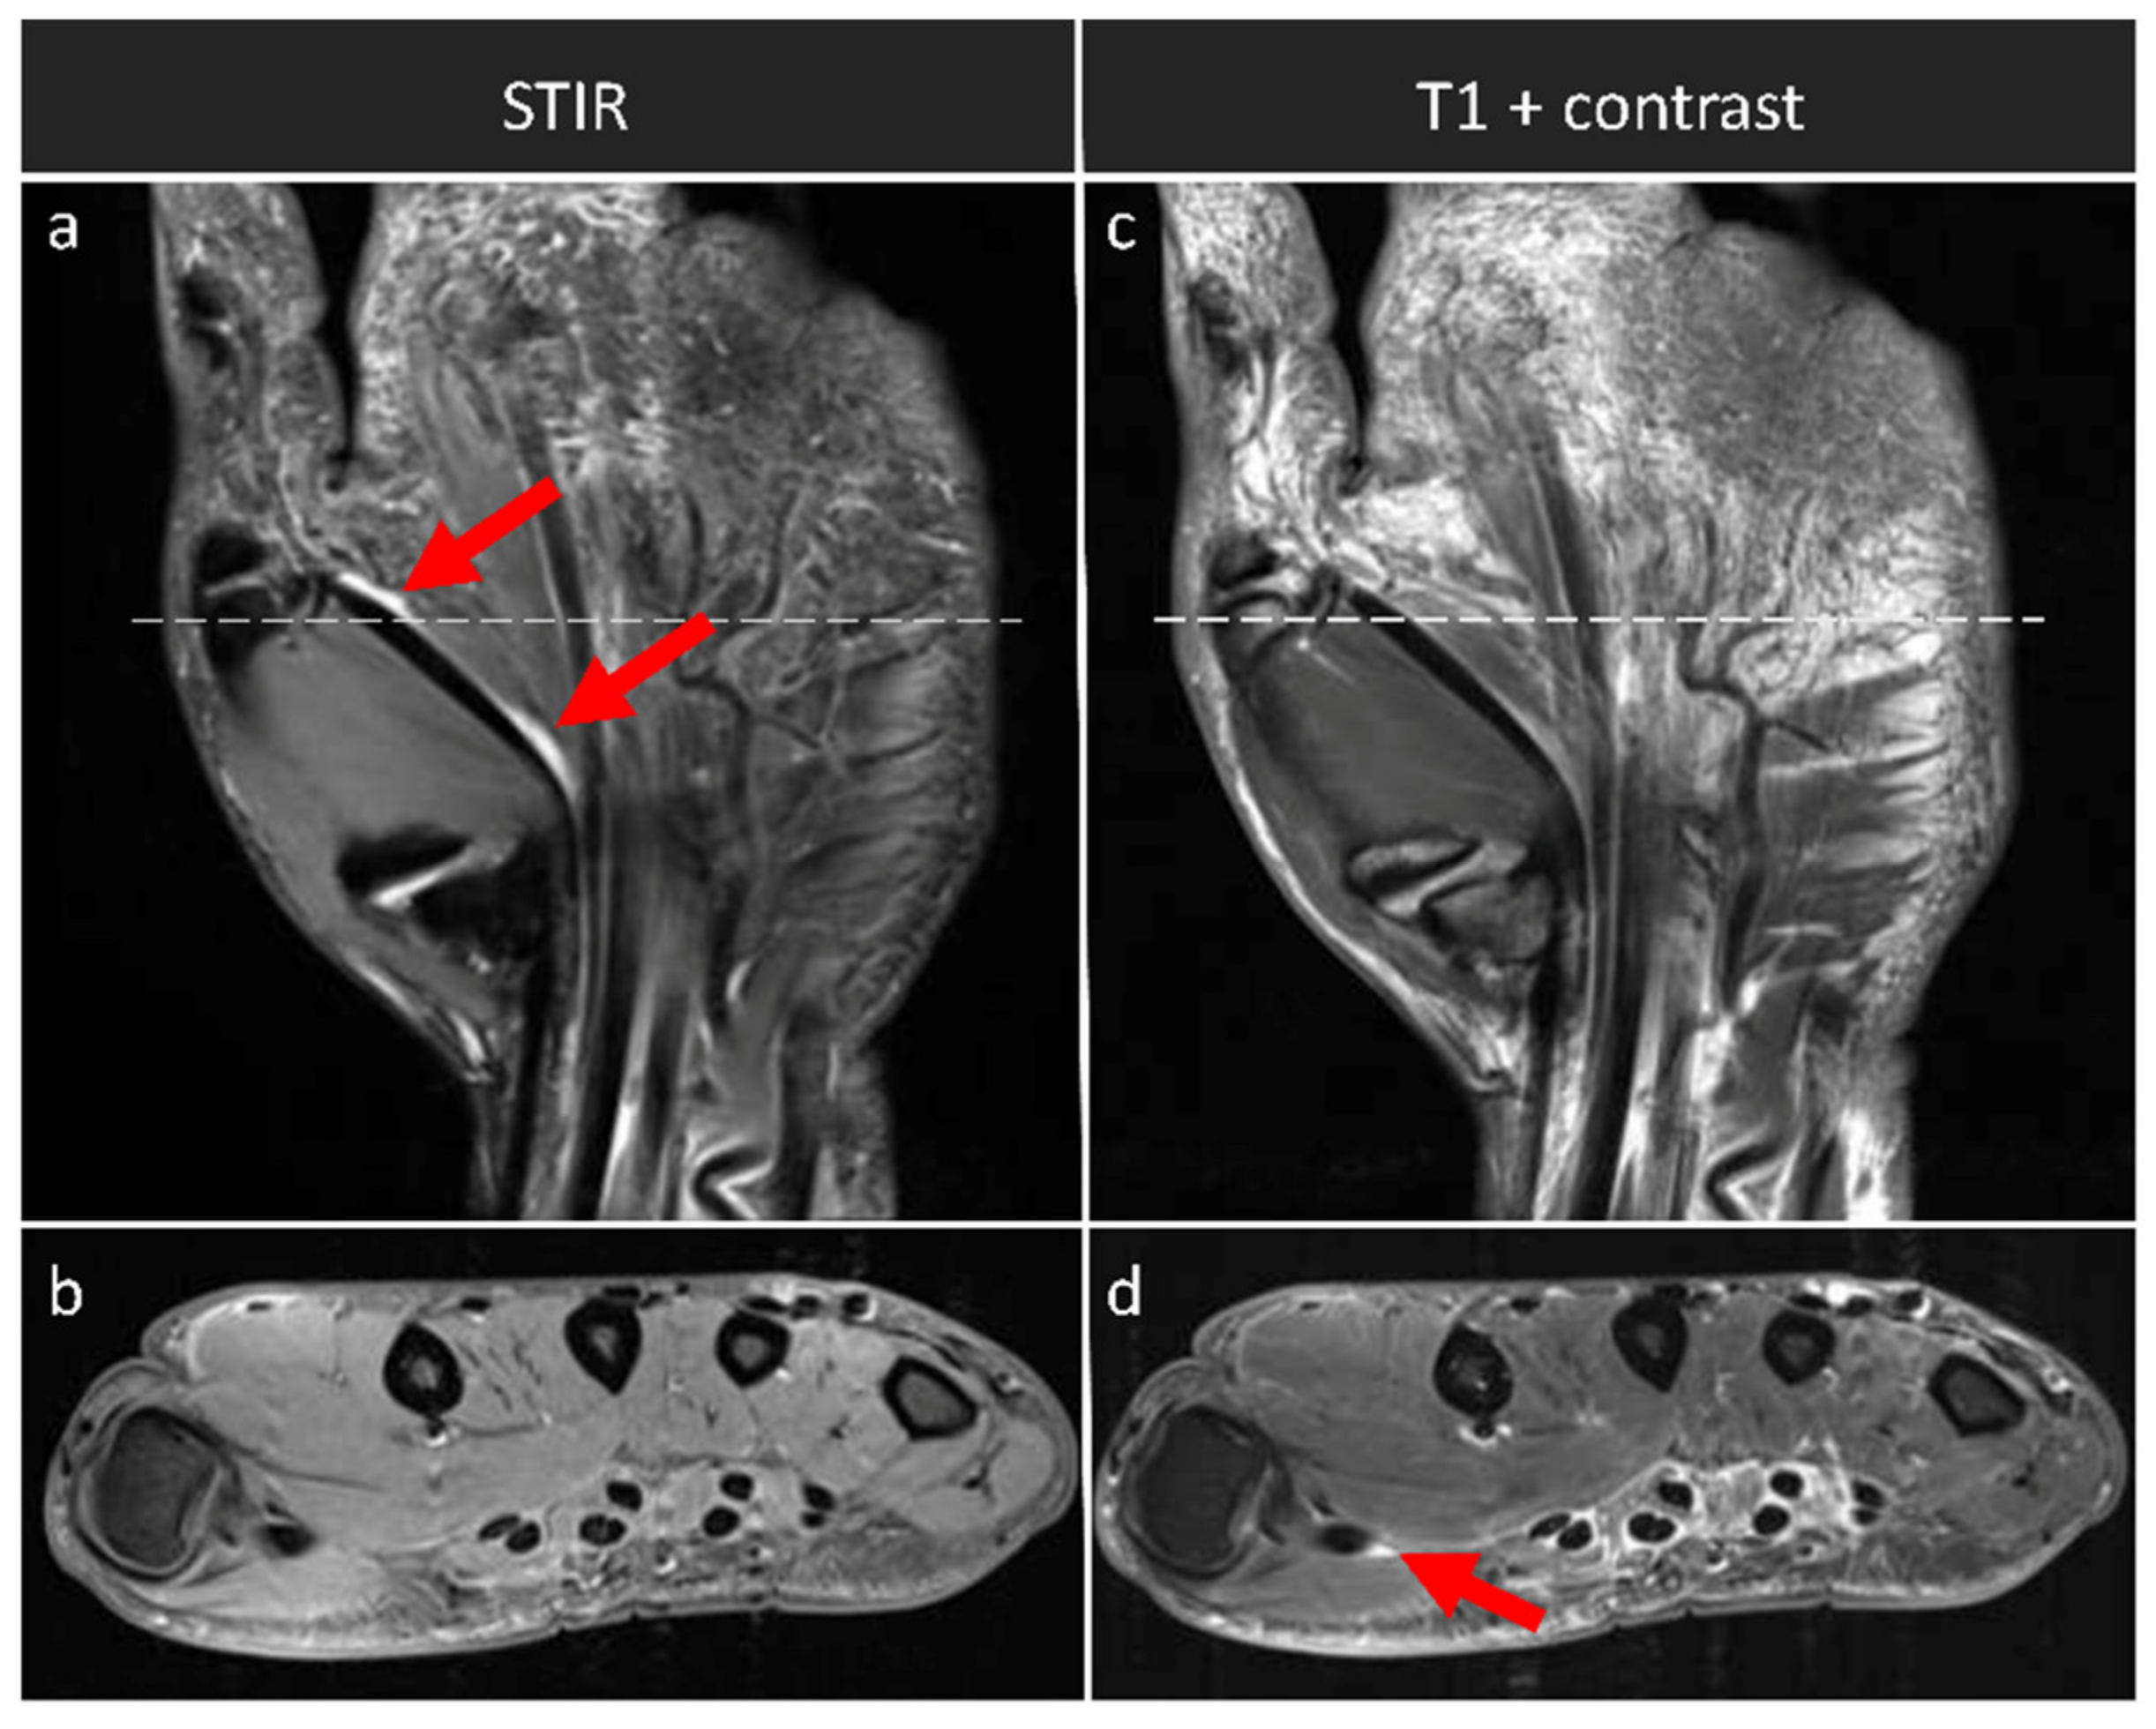

We found a strong and significant correlation for the synovitis subscores, i.e., synovitis-SAFE and synovitis-contrast (ρ = 0.937; p < 0.001). Qualitative comparative evaluation of the STIR and the T1-weighted post-contrast sequences indicated corresponding imaging findings (Figure 2). For the assessment of tenosynovitis, the two subscores, i.e., tenosynovitis-SAFE and tenosynovitis-contrast, correlated only on a medium level, yet still significantly (ρ = 0.380; p = 0.035). Qualitatively, tenosynovitis was visible in the STIR and post-contrast T1-weighted sequences (Figure 3). Between RAMRIS and RAMRIS-SAFE, there was a strong and significant correlation (ρ = 0.976; p < 0.001).

Figure 3. Tenosynovitis in an exemplary patient across the sequences. Coronal STIR (a) and axial T1-weighted sequence with fat suppression, yet without contrast agent application (b) and corresponding coronal (c) and axial (d) T1-weighted post-contrast sequences. Axial images were acquired at the level of distal metacarpal bones (as indicated by the white horizontal lines). Tenosynovitis of the flexor tendon of the first digit can be identified in the STIR sequence (dual red arrows in (a) and in the contrast-enhanced sequences (single red arrow in (d)). Right hand of a 48-year-old male patient.